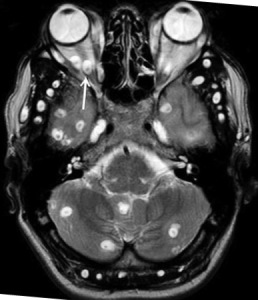

| Фото. А, Б На рентгене и КТ хорошо видно кальцификаты в мышцах и подкожной клетчатке очаги по типу зерен риса по ходу мышечных волокон это цистецерки в мышцах и коже; В На МРТ хорошо видны цистицерки в головном мозге, зрительном нерве (стрелка), в глазных мышцах белые округлые кисты с черным сколексом внутри. | ||||||||||||||||||||||||||||||||||||||||||